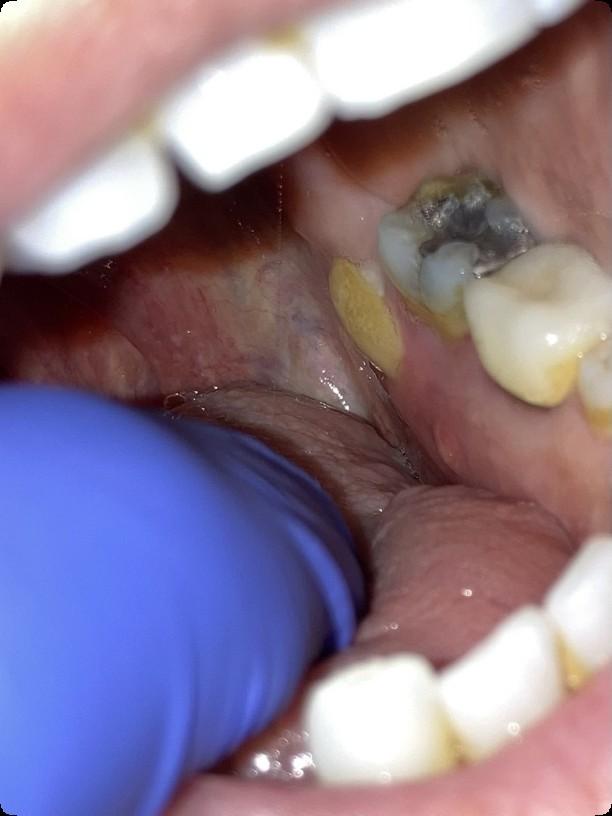

Beyond Myeloma Therapy: Oral Health Survivorship

Katharine (Kate) Ciarrocca, DMD, MSEd

Director, Oral Medicine, Duke University Hospital

Osteonecrosis of the Jaw

MRONJ: Medication Related Osteonecrosis of the Jaw

• Rare oral side effect called osteonecrosis of the jaw that is associated with certain medications, bone-modifying agents.

• Osteonecrosis of the jaw is a condition where small area(s) of the jawbone have difficulty healing and the bone starts to breakdown and die.

What are the signs of MRONJ?

• The hallmarks of ONJ are exposed bone or gum/mucosa/tissue wounds that heal very slowly or do not heal at all for eight weeks or more after an injury to the mouth.

• Some patients report that this begins with a feeling of “roughness” on the gum tissue. If these open wounds become infected, there may be pus or swelling in the adjacent gum tissue.

• Many times, this condition is painless in the beginning, and patients only experience pain after the exposed bone becomes infected.